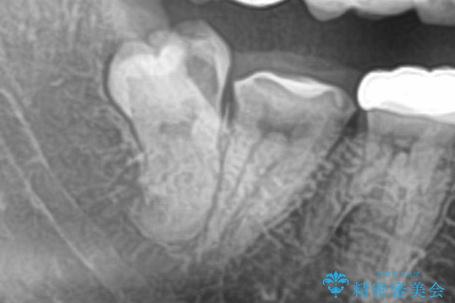

CTで神経の走行位置を確認し、抜歯術を行いました。

親知らずは生え方によっては磨きにくく、虫歯や親知らず周囲の歯肉炎による腫れや痛みを引き起こすため、抜歯をお勧めする場合があります。